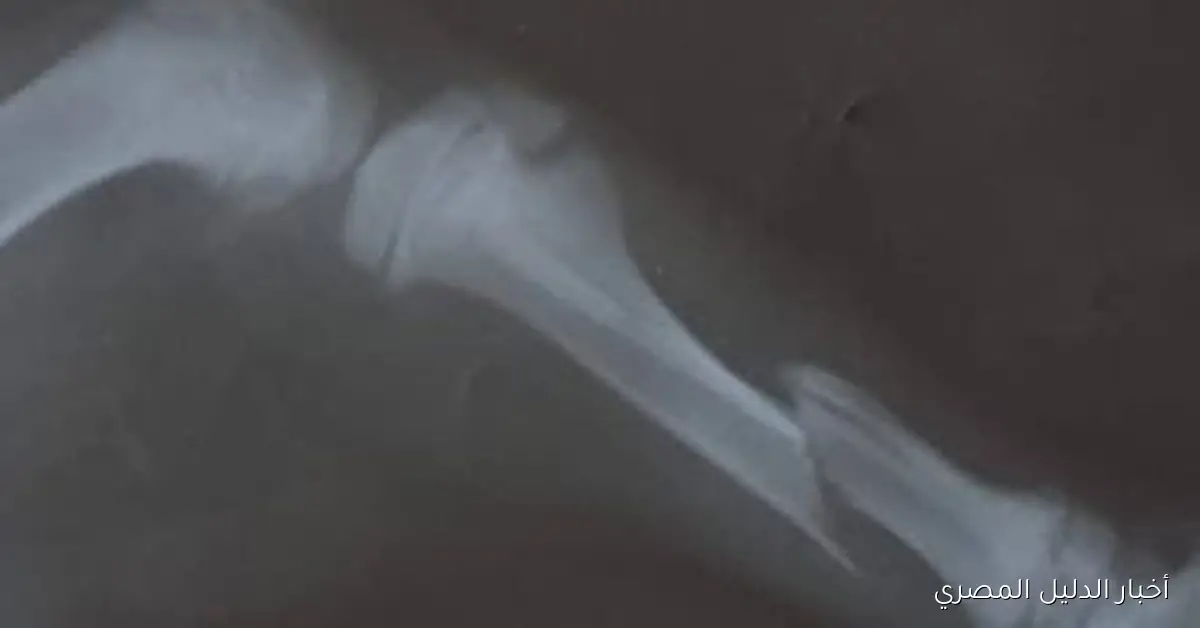

تمكن فريق من الأطباء في مركز طب وجراحة الحيوانات الأليفة بمديرية الطب البيطري في محافظة الغربية من إجراء عملية ناجحة لإعادة تثبيت كسر في ساق كلب يبلغ من العمر ثلاثة أشهر، والذي تعرض لحادث سيارة، ويعكس هذا الإنجاز الجهود المستمرة لأطباء المركز في تقديم خدمات متميزة لعلاج الحيوانات الأليفة وحالات الطوارئ.

عند استقبال الكلب في العيادة، تبين أنه يعاني من كسر في الساق اليمنى نتيجة الحادث، حيث تولى إجراء العملية فريق مكون من الدكتورة سحر الشافعي والدكتورة مروة نافع والدكتور محمد الخولي، وبعد العملية، يتم متابعة الحالة للتأكد من استقرارها وتقديم العلاج اللازم، مع توقعات بعودة الكلب إلى حياته الطبيعية والتعافي في وقت قريب.